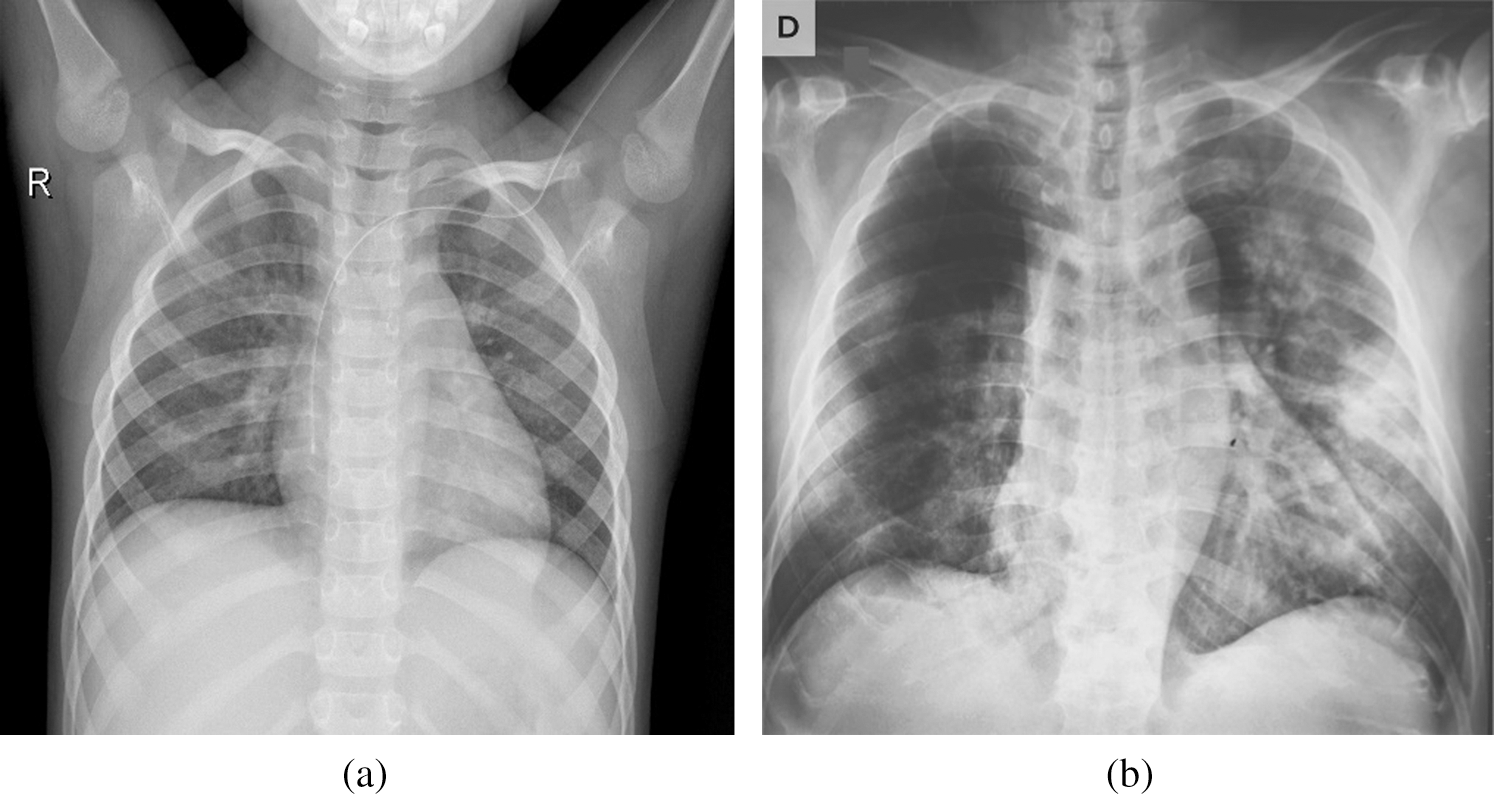

Fig. 2 shows COVID-19 samples and normal large-scale COVID-19 X-ray cases. The number of cases of COVID-19 is regularly updated with new X-ray imaging with a reported COVID-19 infection available, and the full dataset is publicly available at https:/gitub.com/AlaaSulaiman/COVID19-vs-normal-dataset for academic purposes. To prevent overfitting problems and to increase the potential for generalization of the last trained model, a data augmentation technique is used. Next, the image’s size is rescaled to (224 to 224) pixels, and then five random image areas of (

Figure 2: Samples of X-ray dataset (a) normal case (b) positive COVID-19 case